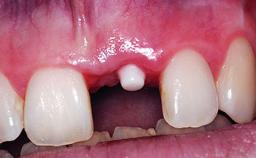

Replacement of a Failing Upper Right Central Incisor, Ridge Preservation and Late Placement of a NC Bone Level Implant

A 30-year-old patient presented at our clinic with a chief complaint of pain in her endodontically treated right maxillary central incisor (tooth 11) with a post-and-core and a fixed single crown. She had a very high lip line, a medium to thin soft-tissue phenotype, and a medium scalloped gingival contour. She also had high esthetic expectations because of her young age and beautiful smile. However, her expectations were realistic and she understood the risks of the treatment. At the initial clinical examination there was a slight mobility of tooth 11; no fistula was observed. The patient also had a single crown on the adjacent tooth 21. Both restorations were old and esthetically deficient. A digital periapical radiograph showed a very small periapical radiolucency, a thick intraradicular post, and no separation between root fragments.